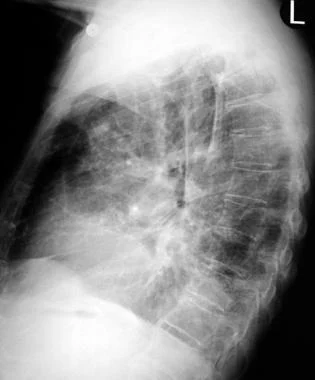

全血分析5分类是什么详解:吸入性肺炎表现、诊断与检测!│临床必备_https://www.jmylbn.com_新闻资讯_第3张

图3 上述(图2)患者的侧位胸片